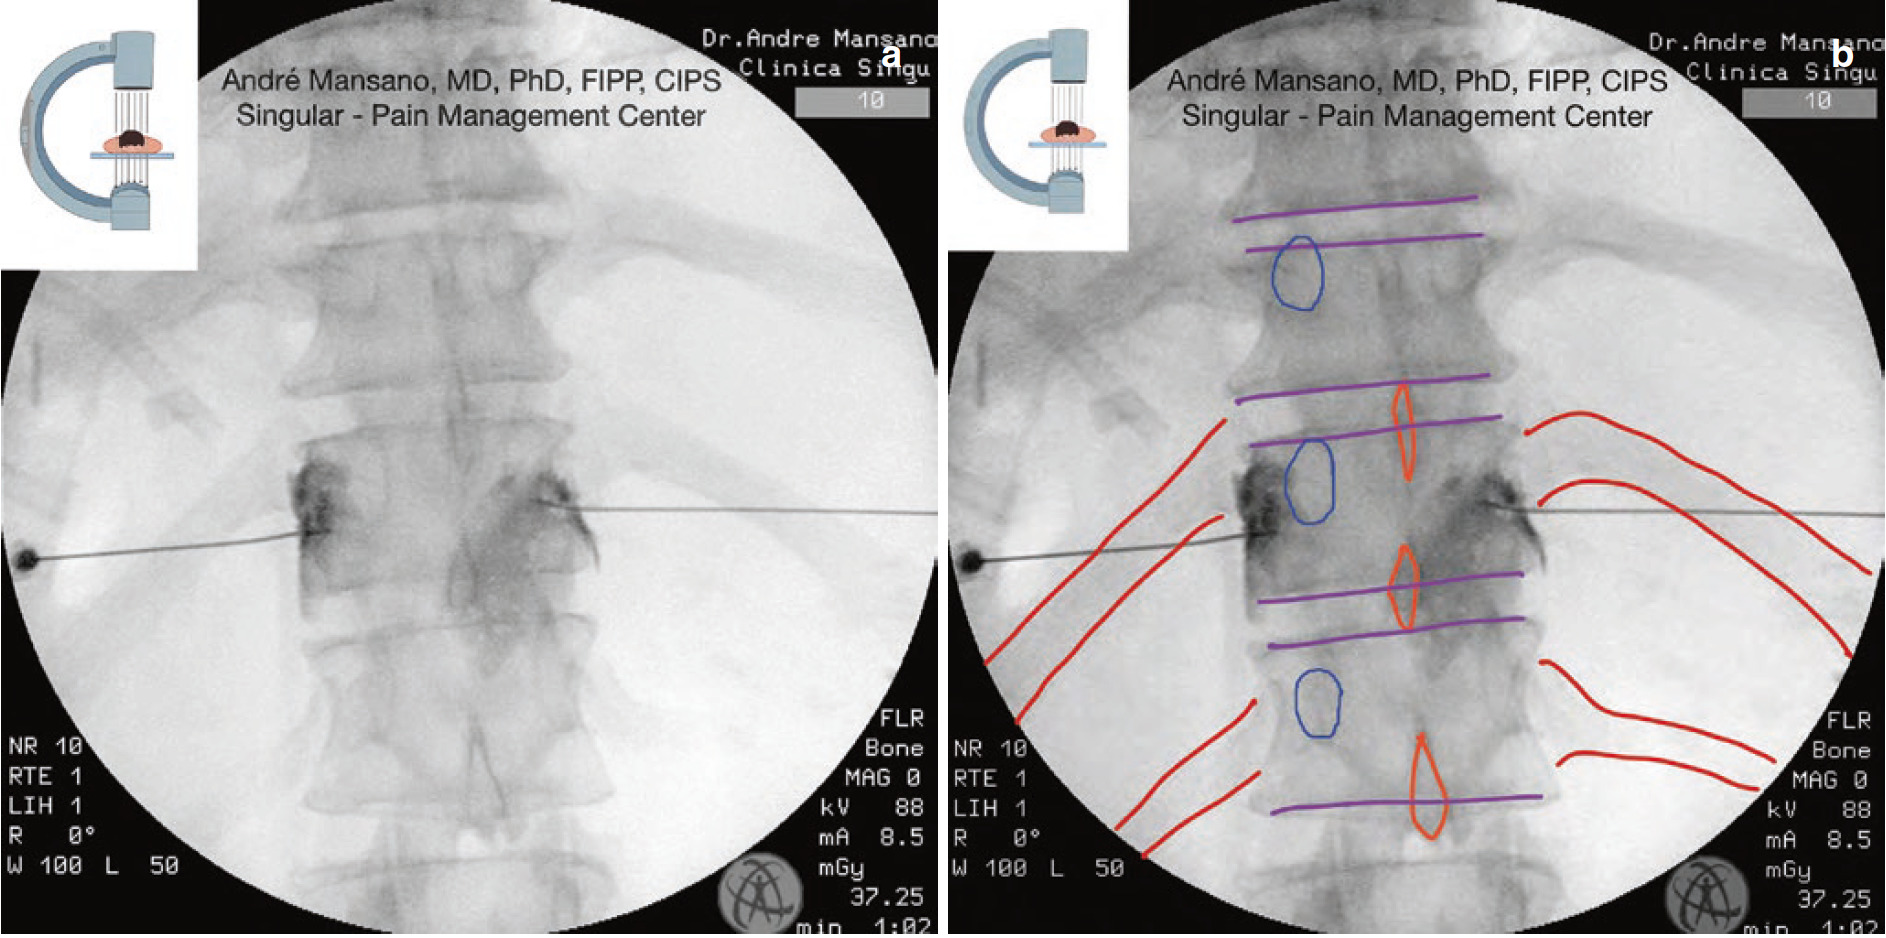

A Radiofrequency ablation at L5 (AP view). Download Scientific Diagram Radiofrequency Ablation Pubmed Radiofrequency ablation (rfa) has emerged as a popular intervention for chronic pain management, including pain originating in the sacroiliac joint. Review the complications of radiofrequency ablation. Radiofrequency ablation (rfa) is an interventional procedure that provides pain relief by using thermal energy to disrupt peripheral. Radiofrequency ablation (rfa) is a treatment modality used in interventional pain management to treat several conditions. Radiofrequency Ablation Pubmed.